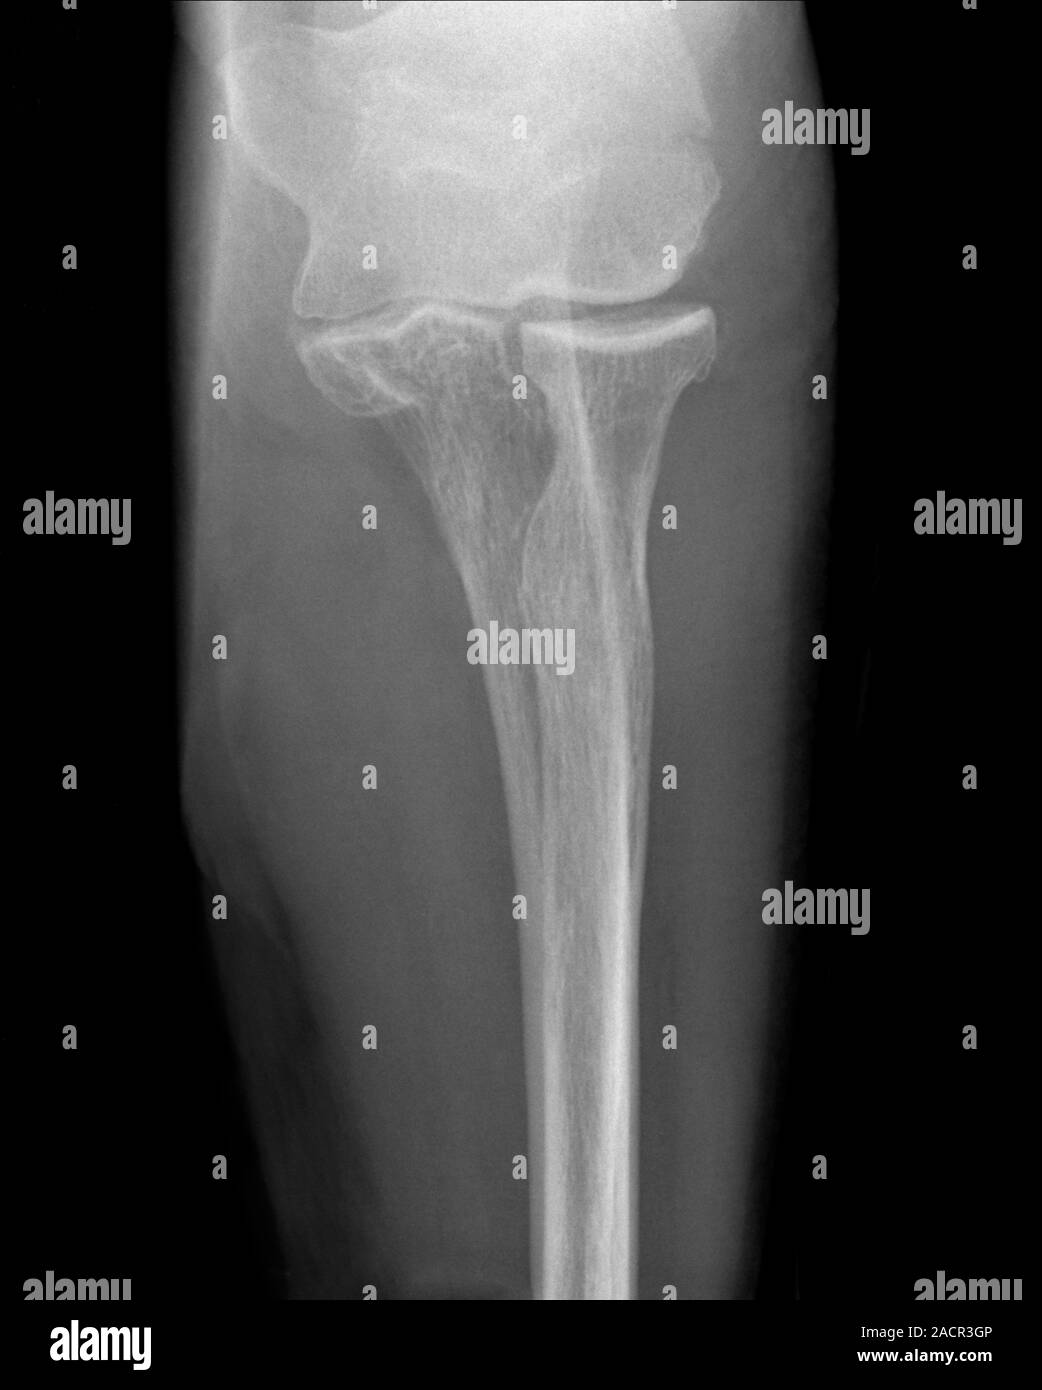

Xray (top view) of a fracture (upper centre) of the upper arm bone Arm Bone Humerus Fracture mechanism of injury. a humerus fracture is the medical name for breaking the bone in your upper arm (your humerus). A broken arm is a bone fracture (broken bone) in your arm. There are several types of humerus fractures, depending on the location of the break. what is a broken arm? We’ll go over the locations of. Arm Bone Humerus Fracture.

Fracture at neck of humerus ( arm bone ) ( film xray left shoulder and Arm Bone Humerus Fracture Fractures of the humerus usually result from falls or direct trauma. We’ll go over the locations of each type. mechanism of injury. a humerus fracture is a break of the humerus bone in the upper arm. A broken arm is a bone fracture (broken bone) in your arm. There are several types of humerus fractures, depending on the. Arm Bone Humerus Fracture.